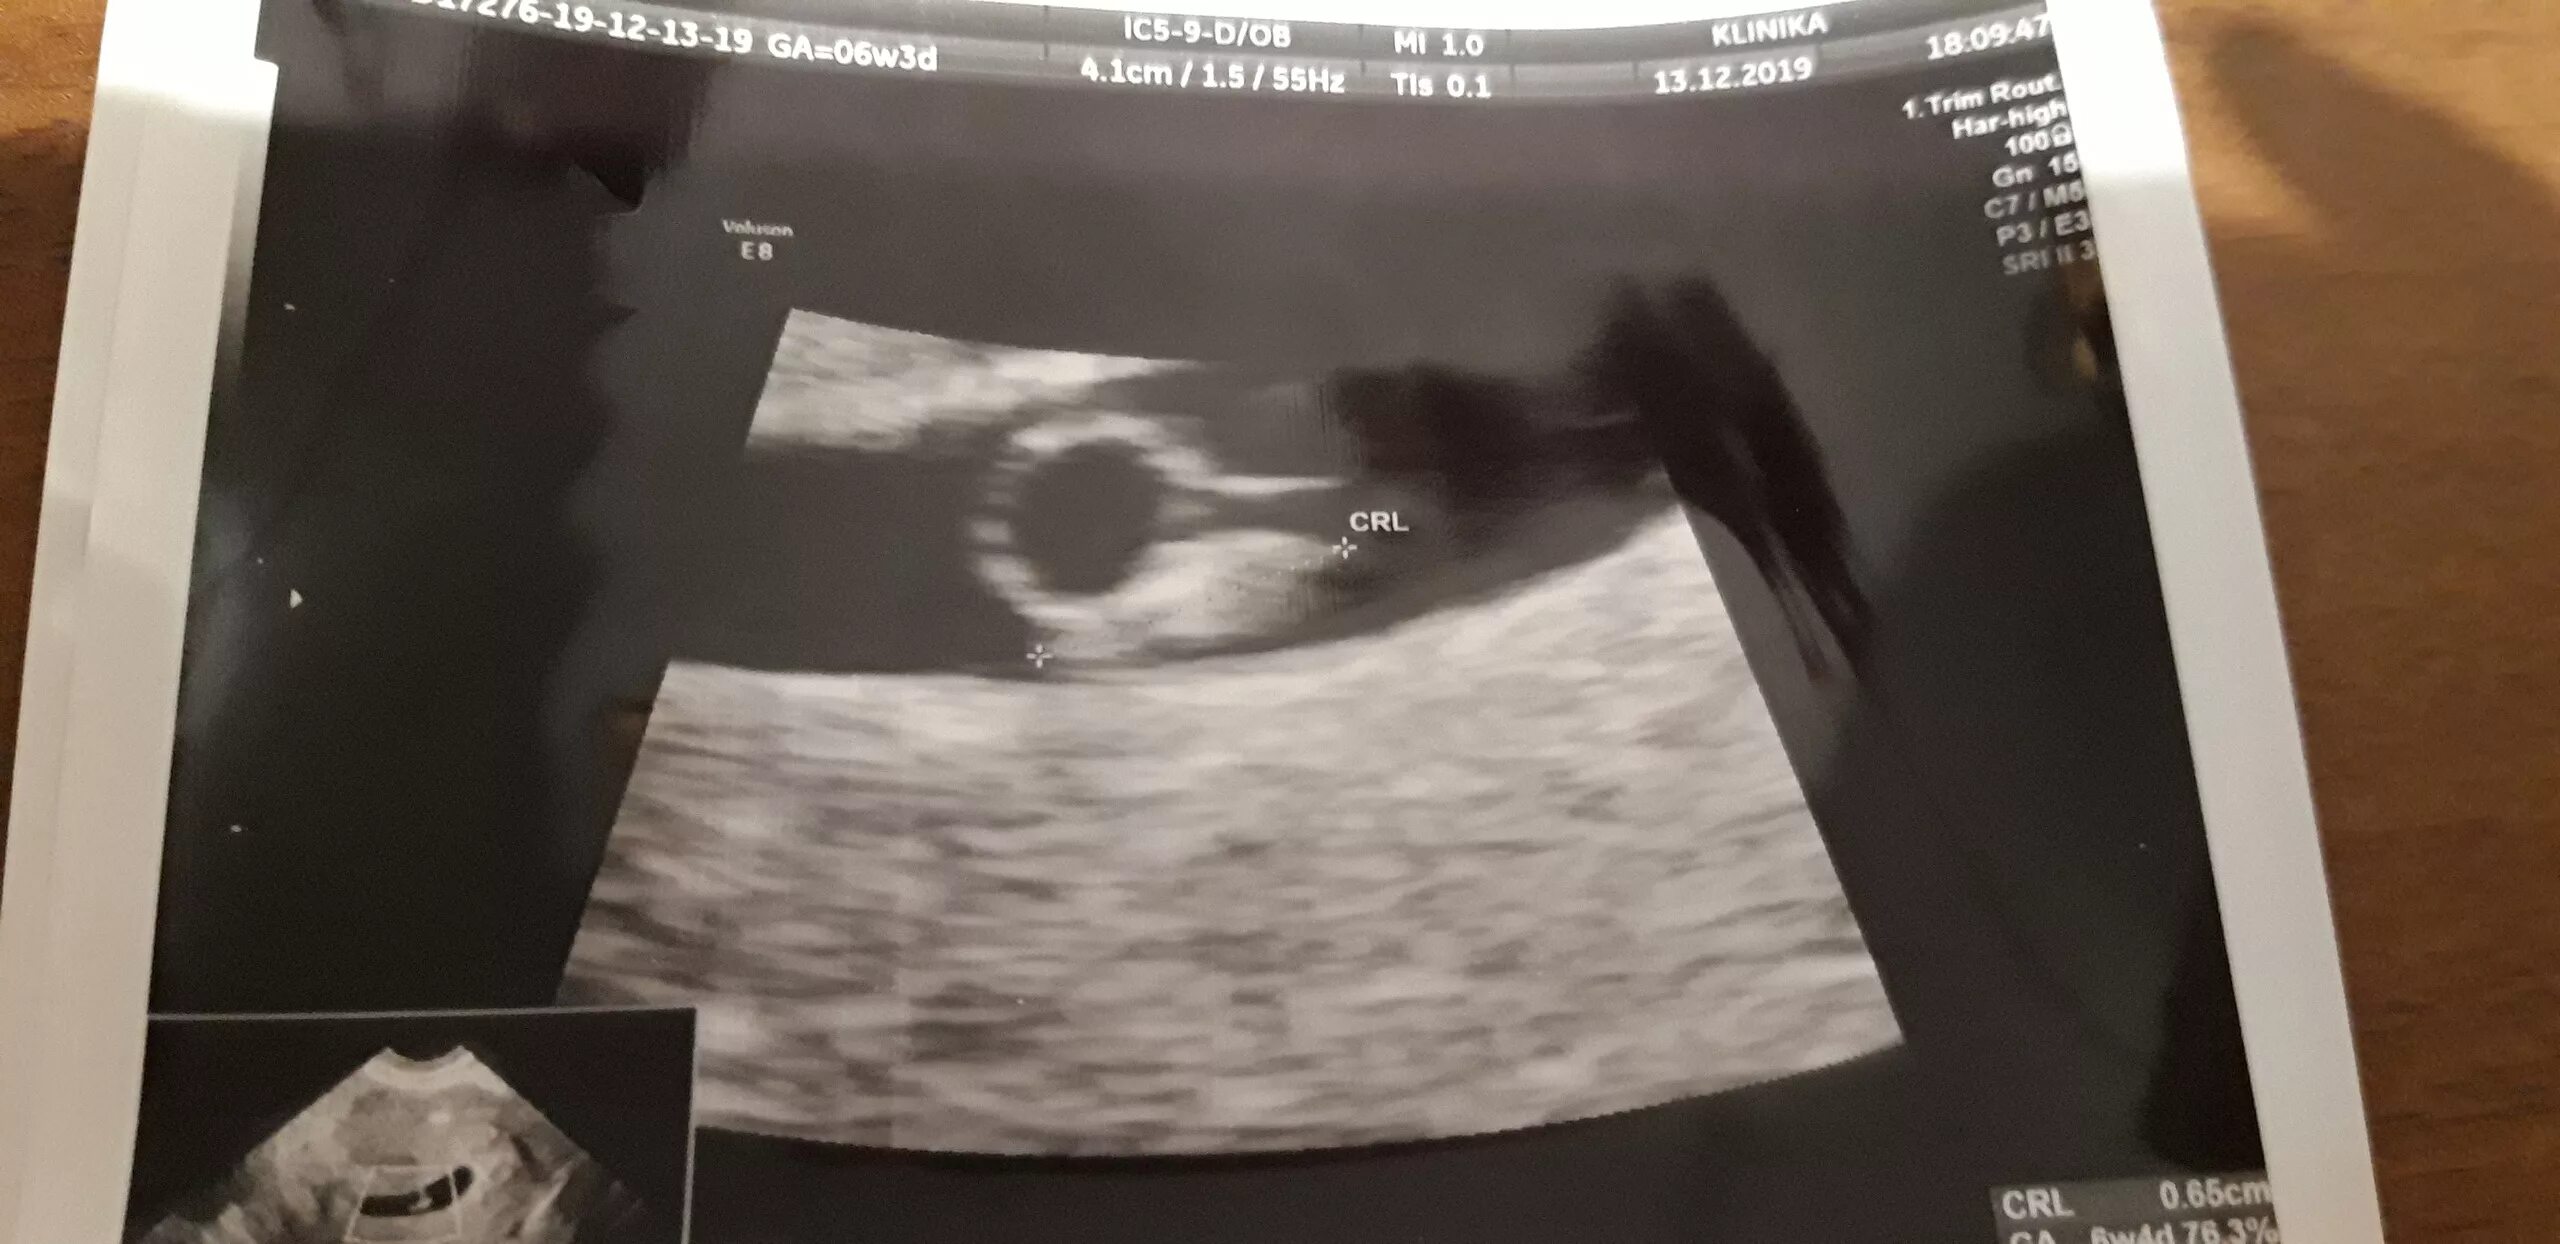

Желточный мешок увеличен